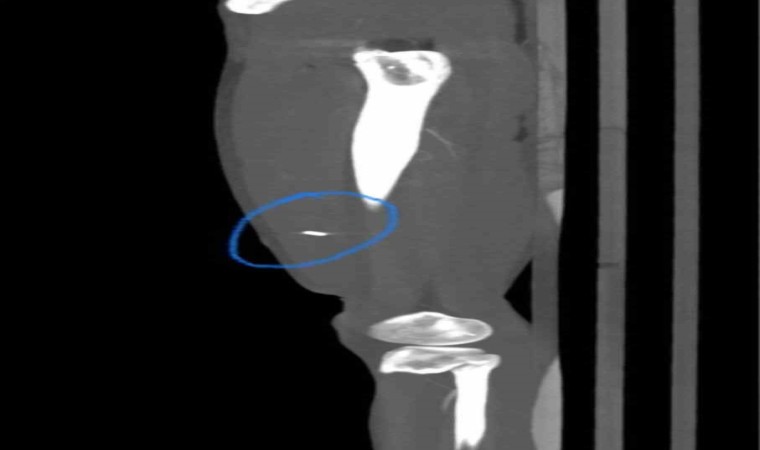

Janttan seken kurşun bekçiyi yaraladı

Dakikalarca süren kovalamacada Kağıthane Ortabayır’daki ana caddeye giren şüphelileri C.B. isimli bekçi, durdurmak için aracın kapısını tuttu. Ancak şahıslar kaçmaya devam edince bekçi birkaç metre sürüklendi. Silahına sarılan bekçi durdurmak istediği aracın lastiğine ateş açtı. Ancak janttan seken kurşun, bekçiyi bacağına isabet ederek yaraladı. Polis ekiplerinin gelmesiyle şüpheliler kıskıvrak yakalandı. Yere yattıkları kelepçelenen şahısların üst aramasında ve aracında herhangi bir şeye rastlanılamadı. Bekçi ise ambulansla hastaneye kaldırılarak tedavi altına alındı. Yaşananlar ise kameralara yansıdı.